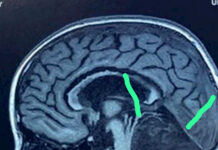

В Бишкеке врачи удалили из мозга восьмилетней девочки клочок волос

В отделении нейрохирургии Наццентра охраны материнства и детства (НЦОМиД) выполнена уникальная операция на головном мозге.

Как сообщили в Минздраве, в операции приняли участие академик НАН...